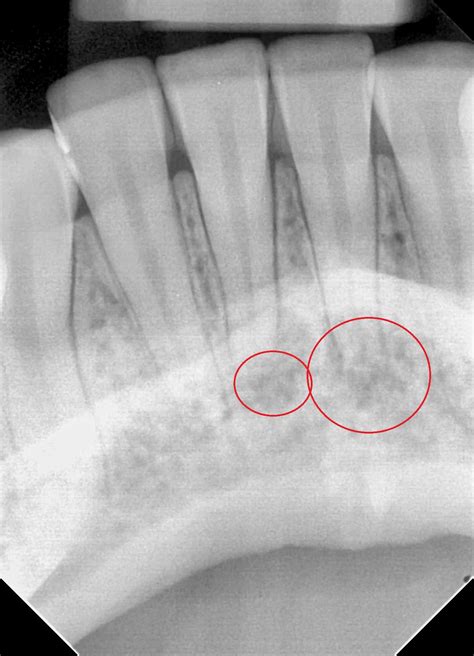

1. Diagnosis and Anesthesia: Your dentist will take X-rays to visualize the internal structure of the tooth. A local anesthetic is administered to ensure the area is completely numb.

A root canal becomes necessary when the soft tissue inside the tooth, called the pulp, becomes infected or inflamed. This often happens due to deep decay, repeated dental procedures, faulty crowns, or trauma to the face. Because front teeth have only one root and one canal, the procedure is often faster and less complex than it is for molars.